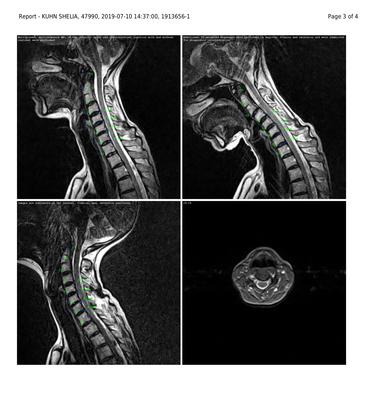

Over the last 20 years, I have lost the ability to extend my right thumb and forefinger. My wrist is very weak. I cannot even pick up a glass of water. I have had multiple MRI's of my shoulder and cervical spine. Nothing has been found. On the last MRI report they reported "Concurrent bilateral uncovertebral joint degenerative change is seen. Disc material and uncovertebral joint degenerative change cause mild left neural foraminal narrowing. Bilateral exiting nerve roots are normal. Disc deformity measures 2.3 mm in neutral 1.9 mm in flexion and 2.3 mm in extension position."

Unfortunately the images and reports are too small to read. Please look: is there any mention of cervical ribs?